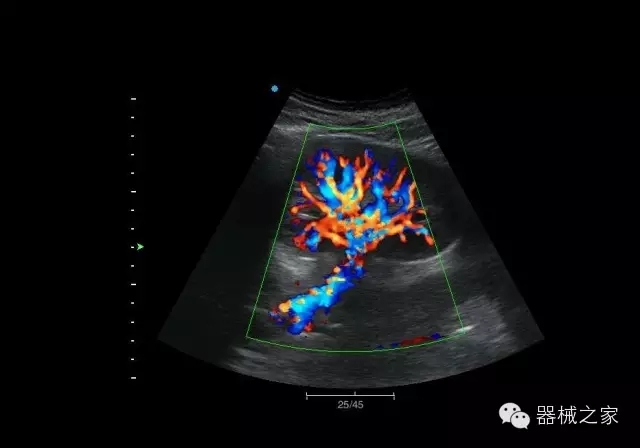

臨床圖片賞析

結(jié)甲

腎臟血流

肝血管瘤

產(chǎn)品特點(diǎn)

·屏幕可左右90度旋轉(zhuǎn);

·雙模操控;

·兩用提手;

·雙鋰電池;

·超輕機(jī)身;

·15寸高亮高清醫(yī)學(xué)顯示器;

·衛(wèi)星布局操控面板;

·一體化剪切板;

·多功能導(dǎo)航鍵;

“宏云”平臺

·采用移植自高端臺式彩超的“宏云”平臺技術(shù),使系統(tǒng)具有更優(yōu)秀的圖像效果;

人性化的設(shè)計(jì)

·內(nèi)置電池,輕巧的外觀設(shè)計(jì)以及臨床功能、軟硬件設(shè)計(jì)的人性化設(shè)計(jì),使系統(tǒng)在臨床多科室移動(dòng)診查中,均從容應(yīng)對;

Fusion THI二代融合諧波成像

·在不同諧波頻率段獲得的信息進(jìn)行實(shí)時(shí)融合,既能獲得諧波圖像分辨率又能提高圖像的穿透力,降低圖像噪音;

XBeam多域復(fù)合成像

·通過頻域和空域角度進(jìn)行復(fù)合的圖像處理,能有效消除由于圖像離散化和圖像衰減引起的空間分辨率下降的不利影響,彌補(bǔ)原有圖像空間分辨率的不足,獲得更加清晰的圖像;